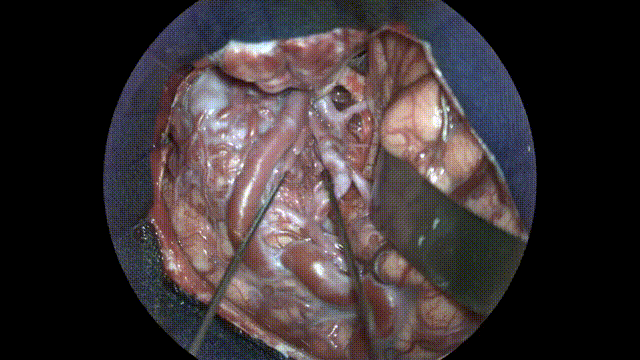

AVM首次評估

圖8:打開硬腦膜后,顳葉上明顯可見AVM,也使用增強現實熒光進行了評估。

視頻1:使用增強現實熒光進行AVM首次評估。外科醫(yī)師能夠在立體視圖下進行操作和探索,同時評估血流。

視頻2:AVM通過更深層次的解剖評估- 清楚地顯示動脈充盈階段。手術期間,增強現實熒光顯示存在需要斷開的瘺管及其與AVM病灶、周圍血管和腦實質的關系。

AVM切除

增強現實熒光有助于了解AVM的表面形態(tài),并確認之前決定的手術策略。

在對AVM進行初步評估后,Chaddad教授采用銳器解剖法在蛛網膜間隙打開了側裂。他將額葉與顳葉分開,以便更好地暴露AVM,并暴露大腦中動脈,這是AVM的主要供血血管。

增強現實熒光實時顯示了流經血管和腦實質的血流,這使得在評估解剖結構時可繼續(xù)工作。然后將淺表供血血管和支流與AVM斷開。然后進行深層周向解剖,凝血并切斷供血血管,以逐漸減少流經AVM的流量。